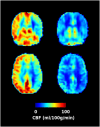

Hemodialysis is a life-saving treatment for patients with kidney failure. However, patients requiring hemodialysis have a 10-20 times higher risk of cardiovascular morbidity and mortality than that of the general population. Patients encounter complications such as episodic intradialytic hypotension, abnormal perfusion to critical organs (heart, brain, liver, and kidney), and damage to vulnerable vascular beds. Recurrent conventional hemodialysis exposes patients to multiple episodes of circulatory stress, exacerbating and being aggravated by microvascular endothelial dysfunction. This promulgates progressive injury that leads to irreversible multiorgan injury and the well-documented higher incidence of cardiovascular disease and premature death. This review aims to examine the underlying pathophysiology of hemodialysis-related vascular injury and consider a range of therapeutic approaches to improving outcomes set within this evolved rubric..